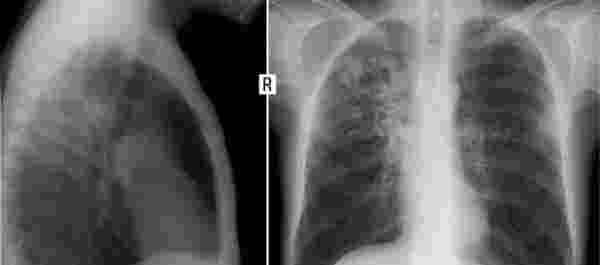

除此以外,茶煙是茶葉的提取物,因此它和煙草屬于類似的干葉物質,那么這種東西燃燒后一定會產生煙霧,煙霧的主要成分是可吸入顆粒物,大約是PM2.5-PM10,這都是肺部能夠吸入的顆粒物。

當這些固體顆粒物進入肺部后能完全堵塞肺泡,從而影響肺部的擴張,像上文的王大爺,本來就有肺結節,如果繼續吸茶煙,那么結節會越來越大,加快肺癌的進程。